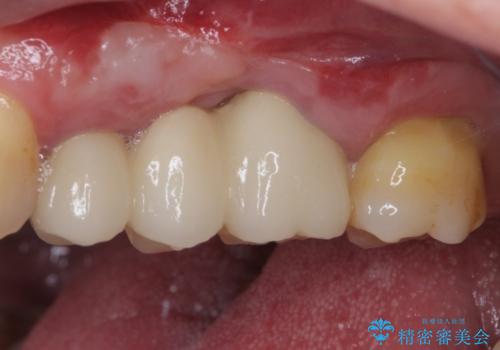

抜歯後、骨吸収量が多く、歯肉のラインが不揃いとなっているため骨造成術を、硬い歯肉が失われて清掃性が低下するため角化歯肉の移植術を行い、また並行して支台歯の根管治療を行っていき、環境を整えた上でオールセラミックブリッジにて補綴治療を行うこととしました。

インプラントによる補綴治療も検討しましたが、骨吸収量が多いこと、後方の支台歯が今後抜歯となる可能性が否定できないことを鑑み、将来抜歯となった際にインプラント2本を埋入することで患者様と事前にお話をしました。